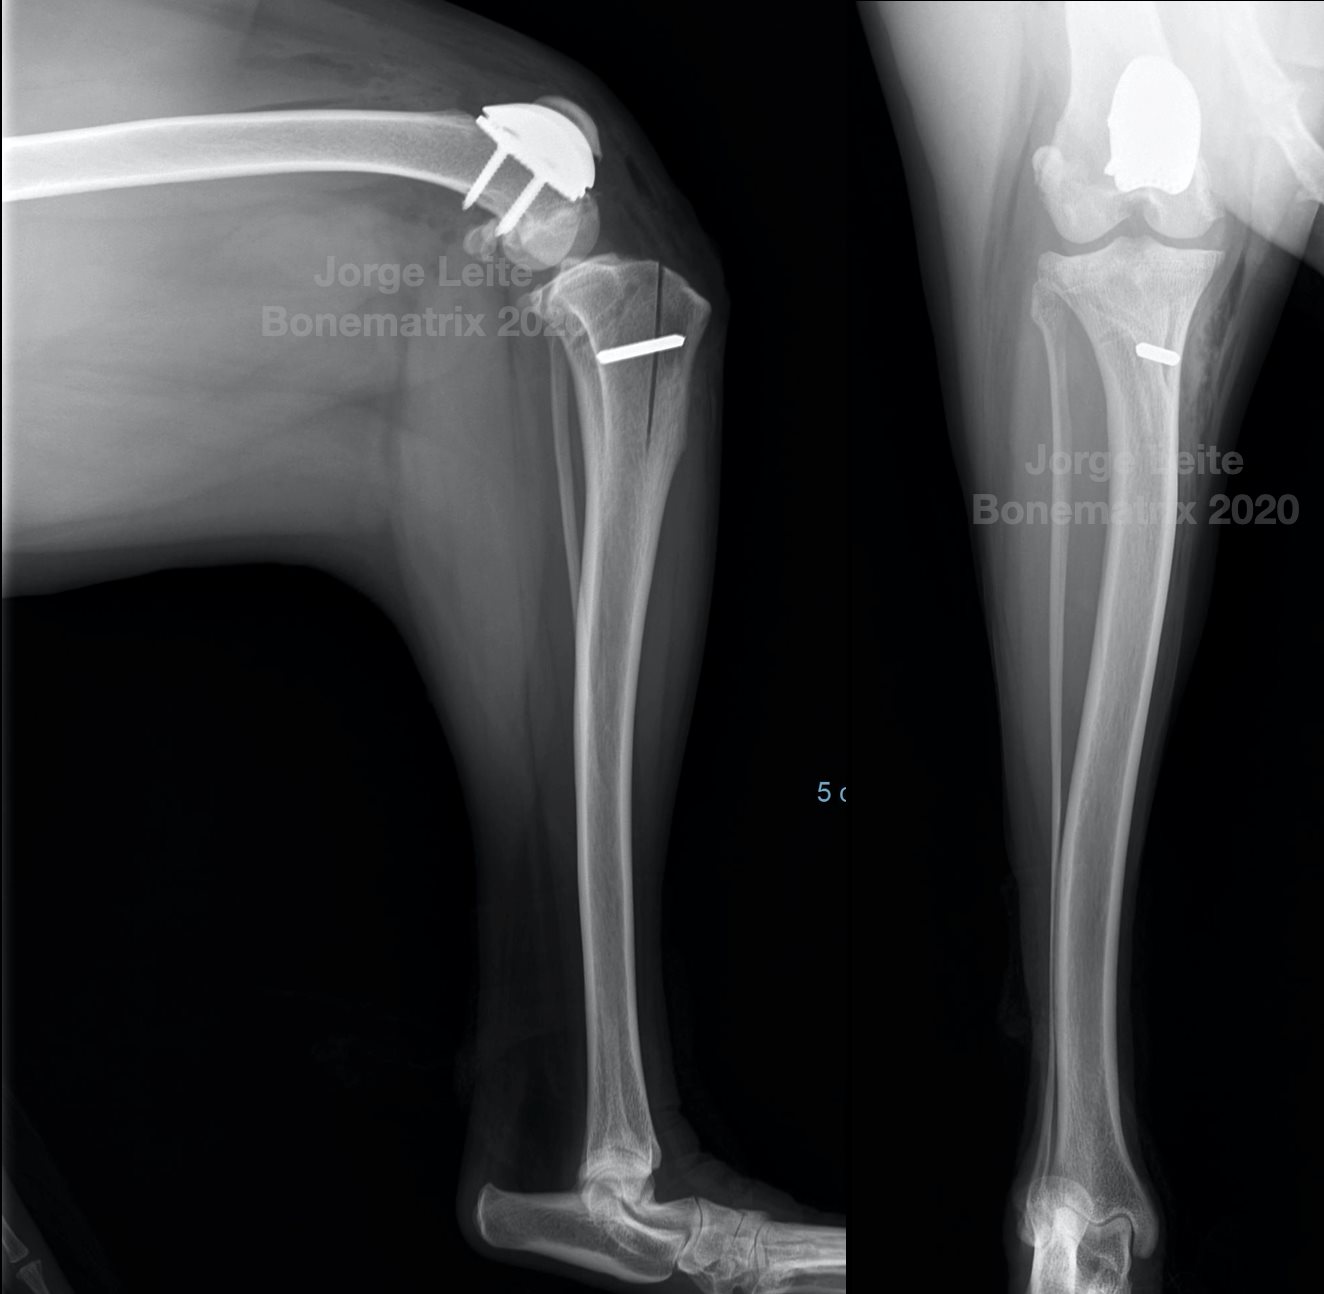

Mesmo cão, necessidades diferentes para tratamento de luxação medial de patela nos dois joelhos.

Luxação medial de patela grau II com severo desconforto de joelho devido a erosão de cartilagem e osteoartrite.

Plano cirúrgico: PGR + TTTT

• 22º de anteversão femoral

• 99º de aLDFA com severa erosão cartilagínea

• 10º de torção tibial externa estimada